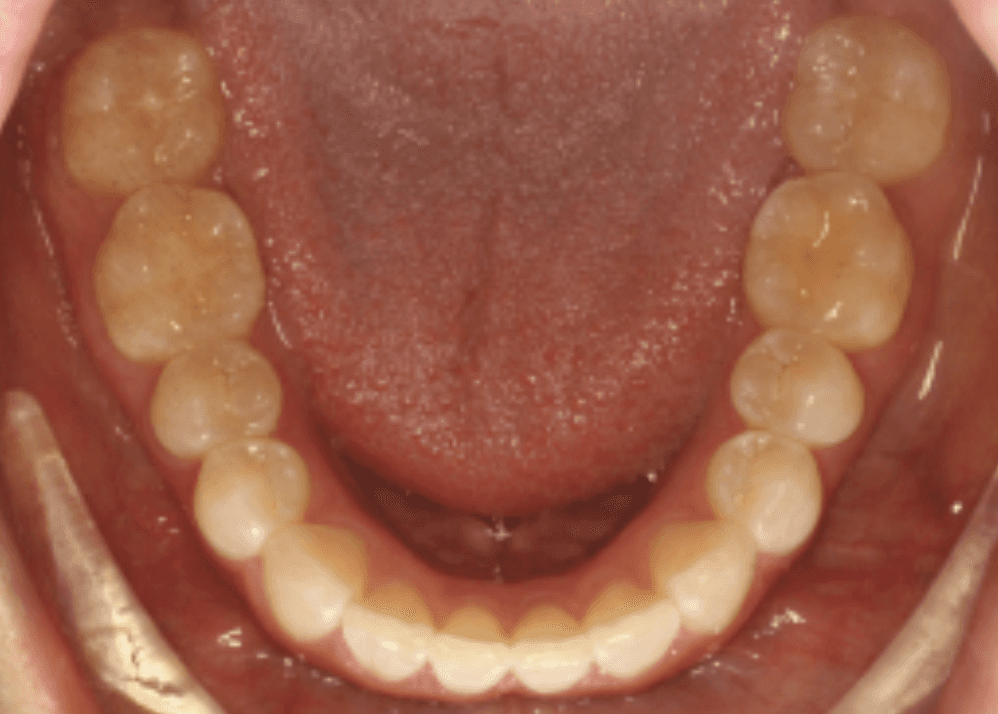

Diagnosis: Deep bite, lower anterior crowding, rotated upper lateral, arch misalignment, wear on teeth from grinding

Initial treatment

INTRAORAL